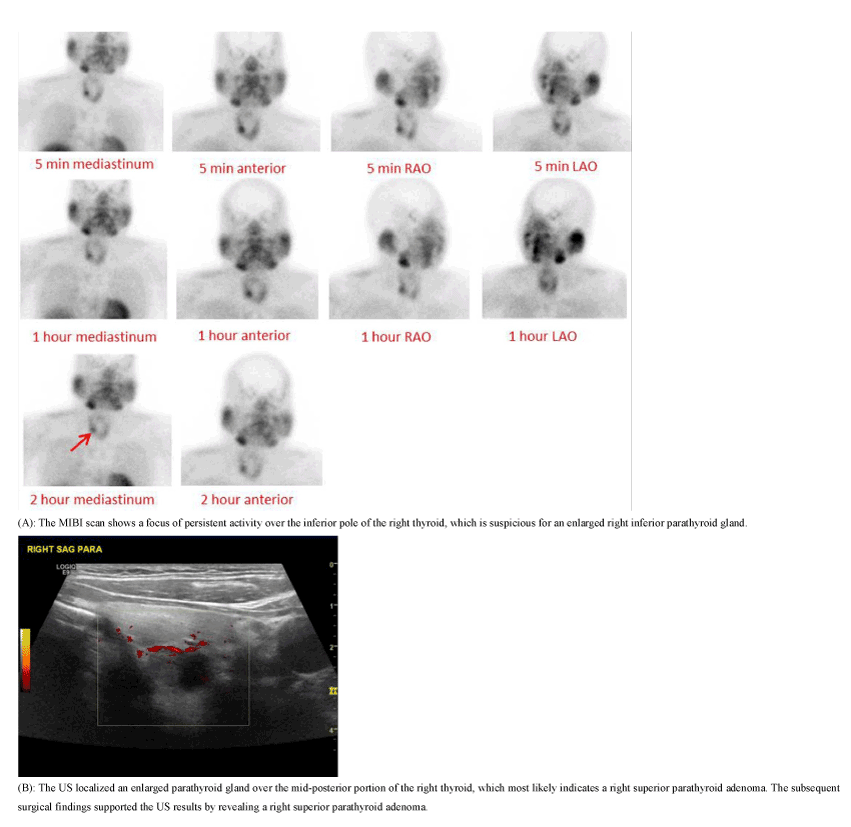

Figure 3. A 49-year-old female presented with a PTH level of 192.5 pg/ml and a calcium level of 11.1 mg/dl.